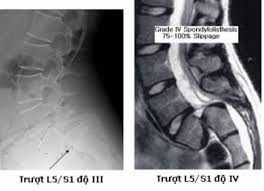

Việc đầu tiên trong chẩn đoán trượt đốt sống là khám sức khỏe. Nếu bị tình trạng này, bạn sẽ rất khó để duỗi chân thẳng trong các bài kiểm tra. Chụp X-quang thắt lưng dưới giúp xác định xem đốt sống có bị trượt ra khỏi vị trí không và có xuất hiện tình trạng gãy xương không.

Bác sĩ có thể yêu cầu chụp CT scan nếu nghi ngờ đốt sống di lệch đè lên dây thần kinh.